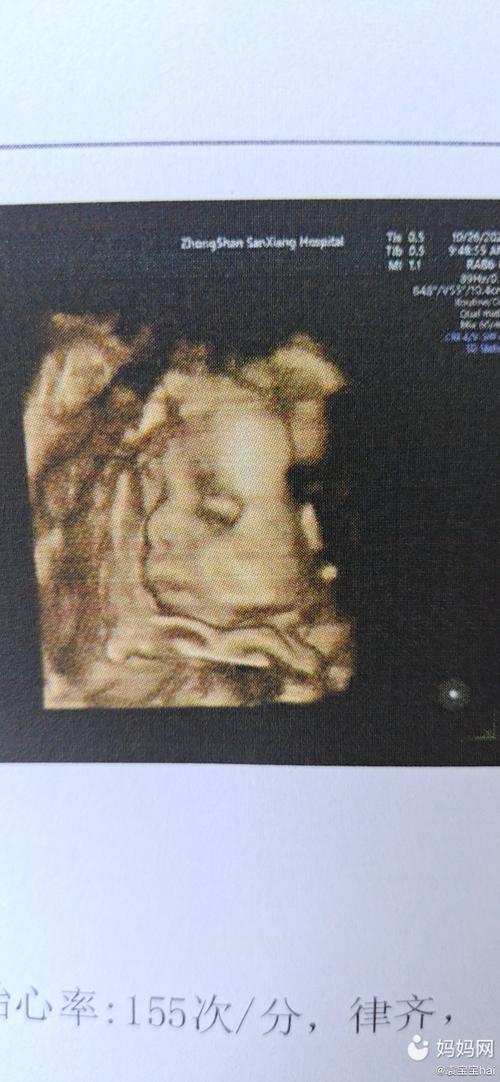

四维一次性过了!小小的你,和爸爸长这么像!

这是四维的照片,和爸爸简直太像了,快看看出生后像谁呀?